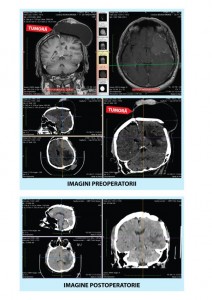

Pacient cu meningiom cerebral recidivat operat cu succes dupa ce a fost calificat ca fiind "inoperabil"O echipă medicală a Centrului de Neurochirurgie Spinală și Cerebrală NeuroLife, centru de excelență în domeniul neurochirurgiei ce aparține Sistemului Medical MedLife, a efectuat cu succes o intervenție de îndepărtare a unei tumori cerebrale unui pacient de 60 de ani. Pacientul a fost diagnosticat cu meningiom cerebral atipic recidivat, localizat fronto-parietal, pe partea stângă.

Înainte de a fi preluat de medicii centrului NeuroLife, pacientul a suferit trei intervenții chirurgicale de îndepărtare a tumorii, însă în ciuda operațiilor, a tratamentelor de tip radioterapie și a controalelor periodice, aceasta recidiva mereu în alte zone ale creierului. La sfârșitul anului 2014, un nou meningiom i-a apărut la baza craniului, urmat de încă două meningioame mai mici, în zona frontală, ce i-au afectat mișcările din jumătatea dreaptă a corpului, în special mâna, pe care ajunsese să n-o mai poată folosi deloc.

Pacientul a ales să se opereze în România. Intervenția s-a desfășurat în două etape: prima operație a avut loc în luna august, când au fost extirpate tumorile cele mai mari. În luna septembrie, a urmat partea a doua a operației, când au fost îndepărtate celelalte tumori. Postoperator, controalele imagistice au stabilit o evoluție favorabilă, pacientul și-a recuperat o parte însemnată din abilitățile afectate și urmează ședințe de kinetoterapie și controale imagistice periodice, pentru a preveni recidivele sau apariția formațiunilor tumorale în alte zone ale creierului.